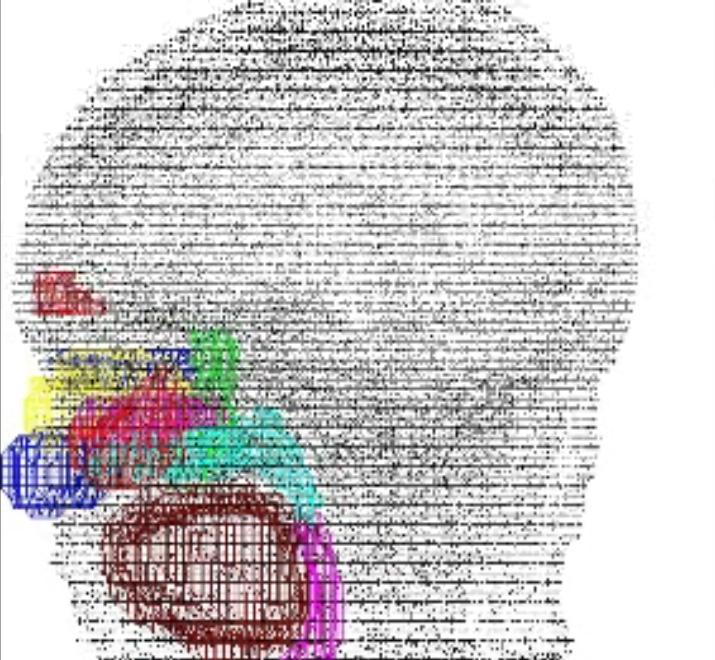

Several inhaled drug formulations were studied by radiolabeling the active ingredient (several different steriods) with C-11 or F-18, formulating that ingredient as the dosage form (different MDI, DPI, and nebulizer formulations), and performing quantitative PET studies of the regional biodistribution and kinetics.

Click on images to see additional examples, larger versions, and videos.